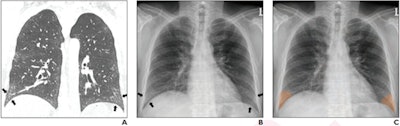

(A) Coronal chest CT shows bilateral lower lobe pleural-based mild reticular opacities with traction bronchiectasis (arrows). (B) Chest radiograph shows subtle corresponding subpleural opacities in basal lung zone bilaterally (arrows). Only one of six readers detected reticular opacity when interpreting radiograph alone. (C) Abnormalities annotated on deep-learning algorithm in basal lung bilaterally with probability of 0.99. Algorithm deemed true-positive for reticular opacity. Five of six readers detected reticular opacity using the algorithm. Image and caption courtesy of the American Journal of Roentgenology.In another interesting result, the radiology residents produced higher sensitivity (97.6%) and accuracy (96.7%) than the board-certified radiologists (90% sensitivity and 94.4% accuracy) when all were using the AI software. All differences were statistically significant (p < 0.001 and p = 0.006, respectively).